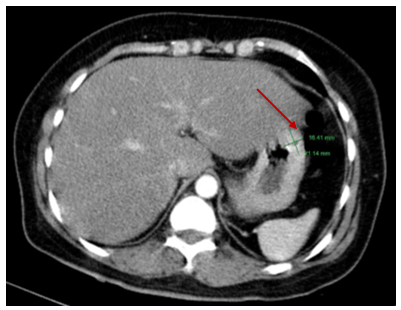

MRI ổ bụng: Nằm trong lớp dưới niêm thành thân vị bờ cong lớn dạ dày, ngay dưới mỏm gan trái có nốt tổn thương kích thước 18x16x25mm, bờ và ranh giới rõ tăng tín hiệu trên T2W, không hạn chế khuếch tán trên DWI/ADC, ngấm thuốc mạnh, tăng dần qua các thì, không thâm nhiễm mỡ xung quanh, không thấy hạch lân cận.

Hình 1. Hình ảnh MRI ổ bụng: ngay dưới mỏm gan trái có nốt tổn thương kích thước 18x16x25mm, bờ và ranh giới rõ tăng tín hiệu trên T2W, không hạn chế khuếch tán trên DWI/ADC, ngấm thuốc mạnh, tăng dần qua các thì, không thâm nhiễm mỡ xung quanh, không thấy hạch lân cận. (mũi tên đỏ)